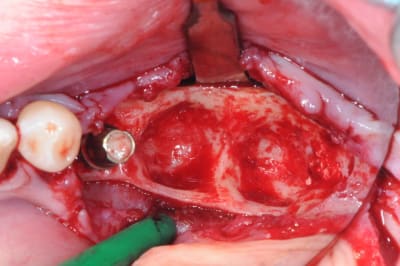

1-2

enfin, mise en place d'une membrane péricarde Jason de 30*50 (je crois)

3- j'ai profité de la stabilité de la mesh comme piquet de tente pour bourrer la cavité avec du MAXGRAFT (os humain)..

4-5- un peu de A-PRF (the king !)

6- le plus important des sutures hermétiques et une gencive immobile en fin d'intervention

7 les radios post-op